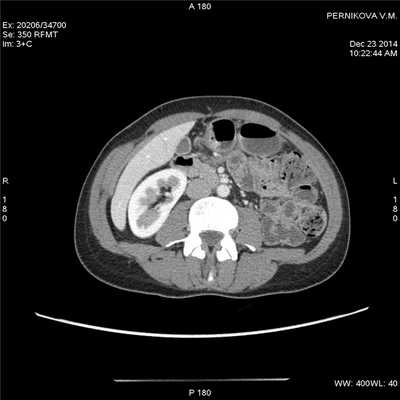

а - болезнь Крона. Отрезок подвздошной кишки сужен, стенка кишки немного утолщена (густая стрелка). Воспалительные тяжи (черная стрелка) в брыжейке тонкого кишечника. Компьютерная томография, аксиальное изображение на уровне пупка.

б - некоторое утолщение стенки двух кишечных петель (пустая стрелка). Воспалительные тяжи в брыжейке тонкого кишечника (длинная стрелка). Воспалительные тяжи в брыжейке напоминают гребень (короткая стрелка) и отражают сосудистые изменения и перилимфатическое воспаление. Компьютерная томография на уровне подвздошных гребней того же пациента, что и на рисунке (а).

(Слева) На КТ, выполненной мужчине 37 лет с обострением хронической симптоматики (боль в животе и диарея), определяется растяжение некоторых сегментов проксимальных отделов тонкой кишки.

(Справа) На КТ у этого же пациента определяется большее количество растянутых петель тонкой кишки, слизистая оболочка которых интенсивно накапливает контраст на фоне подслизистого отека. Визуализируются также группы умеренно увеличенных лимфатических узлов брыжейки (Слева) На КТ у этого же пациента визуализируются два сегмента воспаленной тонкой кишки, разделенные неизмененными участками - классические «прерывистые» поражения при болезни Крона. Обратите внимание на полнокровные прямые сосуды, кровоснабжающие более дистальные отделы воспаленного кишечника.

(Справа) На КТ у этого же пациента визуализируются другие сегменты воспаленного кишечника с контрастным усилением слизистой оболочки, утолщением стенки и сужением просвета. (Слева) На реформатированной корональной КТ у этого же пациента визуализируются отдельные сегменты воспаленной кишки наряду с брыжеечной лимфаденопатией и выбухающими кровеносными сосудами.

(Справа) На корональной КТ у этого же пациента визуализируются воспаленные сегменты кишечника определяется также брыжеечная лимфаденопатия. Диагноз болезни Крона был подтвержден при колоноскопии и биопсии терминальных отделов подвздошной кишки.